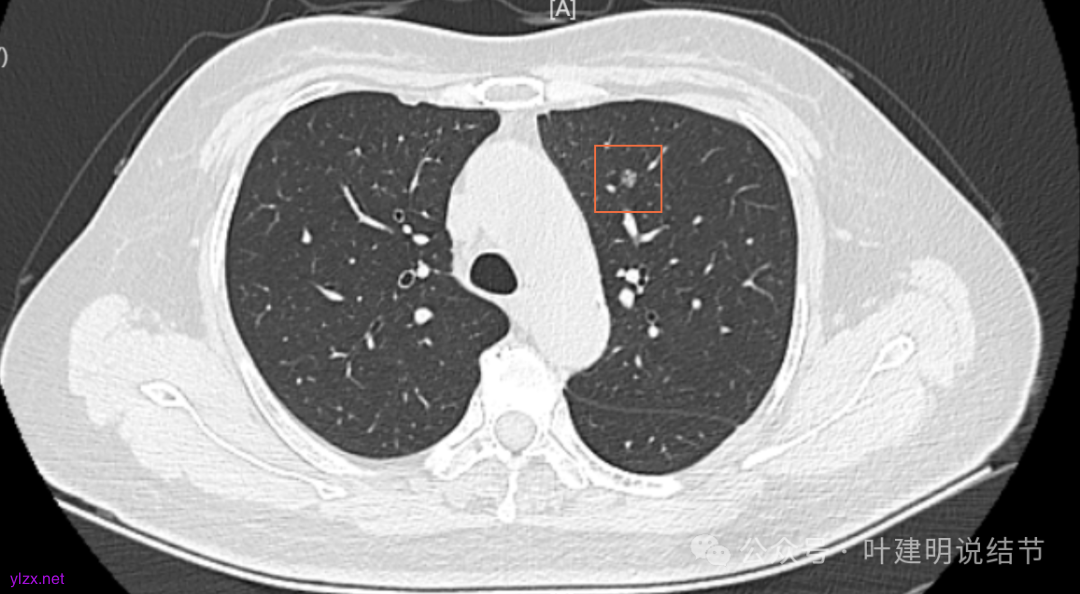

12.2025年4月复查,显示最大结节0.9*0.7。 另外,看几次报告,多发磨玻璃结节数量在上升,从2022年的3个到2025年的7个。

我们发现其实各病灶与三年前比说不上显著进展。

两肺多发磨玻璃结节,主病灶混合密度且有小血管进入,表面不平有毛刺,考虑微浸润性腺癌或浸润性腺癌可能性大,其余部分考虑原位癌或微浸润性腺癌,部分考虑肺泡上皮增生或不典型增生可能。总体上对比2022年说不上太明显的进展。但对于是否手术来讲,我仍倾向当年的意见,左侧的可以考虑近期亚肺叶(个人倾向楔切)切除,右侧的先随访,以后有进展并风险增加再考虑干预处理。因为要拉长两次手术的间隔,这样对机体的创伤与恢复更加有利一些。若定要仍不开刀,则建议要4-6个月复查,不过个人不太主张过于保守随访,对于像主病灶这种有少许实性成分的,不能保证肯定安全。意见供参考!